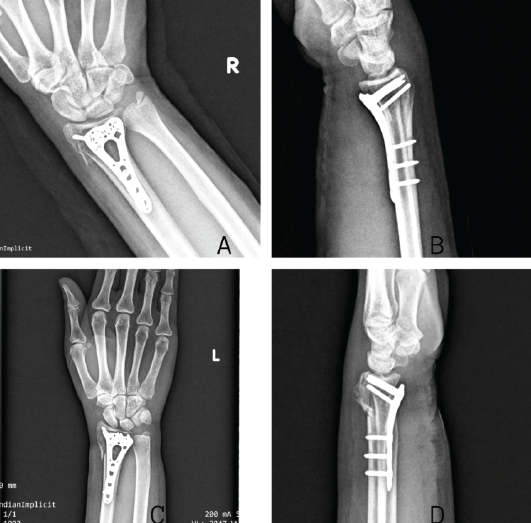

A 42-year-old right-handed male construction worker fell from a scaffold approximately 10 feet high. He landed with both arms outstretched and elbows extended. Upon presentation, the patient had gross deformity, pain, and swelling at both wrists and elbows. Upon inspection, deformities were seen on both wrists and elbows bilaterally. On examination, tenderness was found with a limited range of motion. Neurovascularity was intact in both upper limbs. X-rays revealed bilateral posterior elbow dislocation without associated fracture (Fig. 1a, b, c, d) and bilateral comminuted intra-articular distal radius fractures (AO 23-C2). (Fig. 2a, b, c, d). In the emergency setting, both elbow dislocations were promptly managed with closed reduction under sedation, and concentric reduction was confirmed on post-reduction radiographs (Fig. 3a, b, c, d). Both wrists were also reduced, and stabilization was done with slab application (Fig. 4a, b, c, d). Following initial stabilization and resolution of soft tissue swelling, the patient underwent staged open reduction and internal fixation of the bilateral distal radius fractures using a volar approach (modified Henry technique). Fixation was achieved using volar locking compression plates for both wrists (Fig. 5a, b, c, d).

Figure 5: Post-op X-rays showing appropriate reduction and fixation of the right wrist in anteroposterior (a) and lateral (b) view and left wrist in anteroposterior (c) and lateral (d) view.